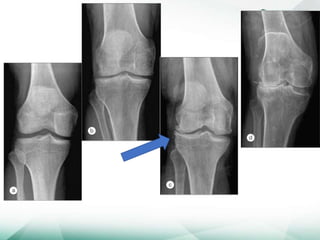

Quatros manifestações:

Estreitamento do espaço articular

Osteófitos

Esclerose subcondral

Cistos subcondrais

• Na OA secundária pode haver alterações da doença

primária

• NÃO HÁ PARALELISMO CLÍNICO-RADIOLÓGICO

Quatros manifestações: Estreitamento doespaço articular Osteófitos Esclerose subcondral Cistos subcondrais • Na OA secundária pode haver alterações da doença primária • NÃO HÁ PARALELISMO CLÍNICO-RADIOLÓGICO